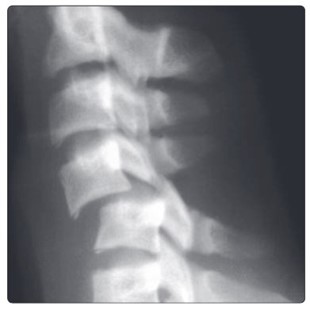

На рентгеновском снимке плотная костная ткань отображается белым цветом, в то время как мягкотканевые структуры, такие как мышцы и подкожно-жировая клетчатка, представлены различными оттенками серого.

При изучении рентгенограмм позвоночника врач-рентгенолог обращает внимание на следующие аспекты:

- Изгибы позвоночного столба. Физиологическими изгибами считаются шейный и поясничный лордозы (изгибы, направленные вперед), а также грудной и крестцовый кифозы (изгибы, направленные назад). Увеличение этих изгибов может указывать на патологию. Отклонение позвонков влево или вправо называется сколиозом;

- Структура и форма позвонков. В норме они выглядят как участки светлого цвета с четким контуром. Тело позвонка на рентгене напоминает прямоугольник с закругленными краями, на которых не должно быть костных разрастаний (остеофитов). В прямой проекции можно увидеть поперечные отростки, которые направлены в стороны от дуги позвонка, а также остистый отросток, расположенный посередине дуги. Остистые отростки в боковых проекциях образуют непрерывную линию;

- Расстояние между позвонками. В норме эти промежутки должны иметь примерно одинаковую высоту, увеличиваясь к поясничному отделу;

- При проведении функциональных проб оценивается взаимное расположение позвонков в крайних положениях сгибания и разгибания позвоночника. В норме смещение позвонков относительно друг друга не должно превышать 1 мм.